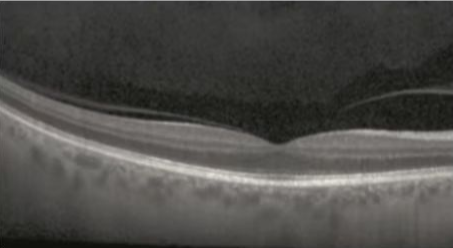

正常黄斑

司法鉴定人通过审阅贾某现有病历资料,进行眼科常规检查、视觉电生理检查,并结合本案具体情况,分析认为:被鉴定人贾某右眼激光笔照射史明确,伤后即出现视力下降,眼底表现为黄斑区出血等新鲜损伤改变,其右眼黄斑损伤与激光笔照射之间存在直接因果关系。

黄斑区位于视网膜中央,是视力最敏锐的区域,负责视觉和色觉的视锥细胞就聚集于该区域。任何累及黄斑部的病变都会引起中心视力的明显下降、视物色暗、变形等。